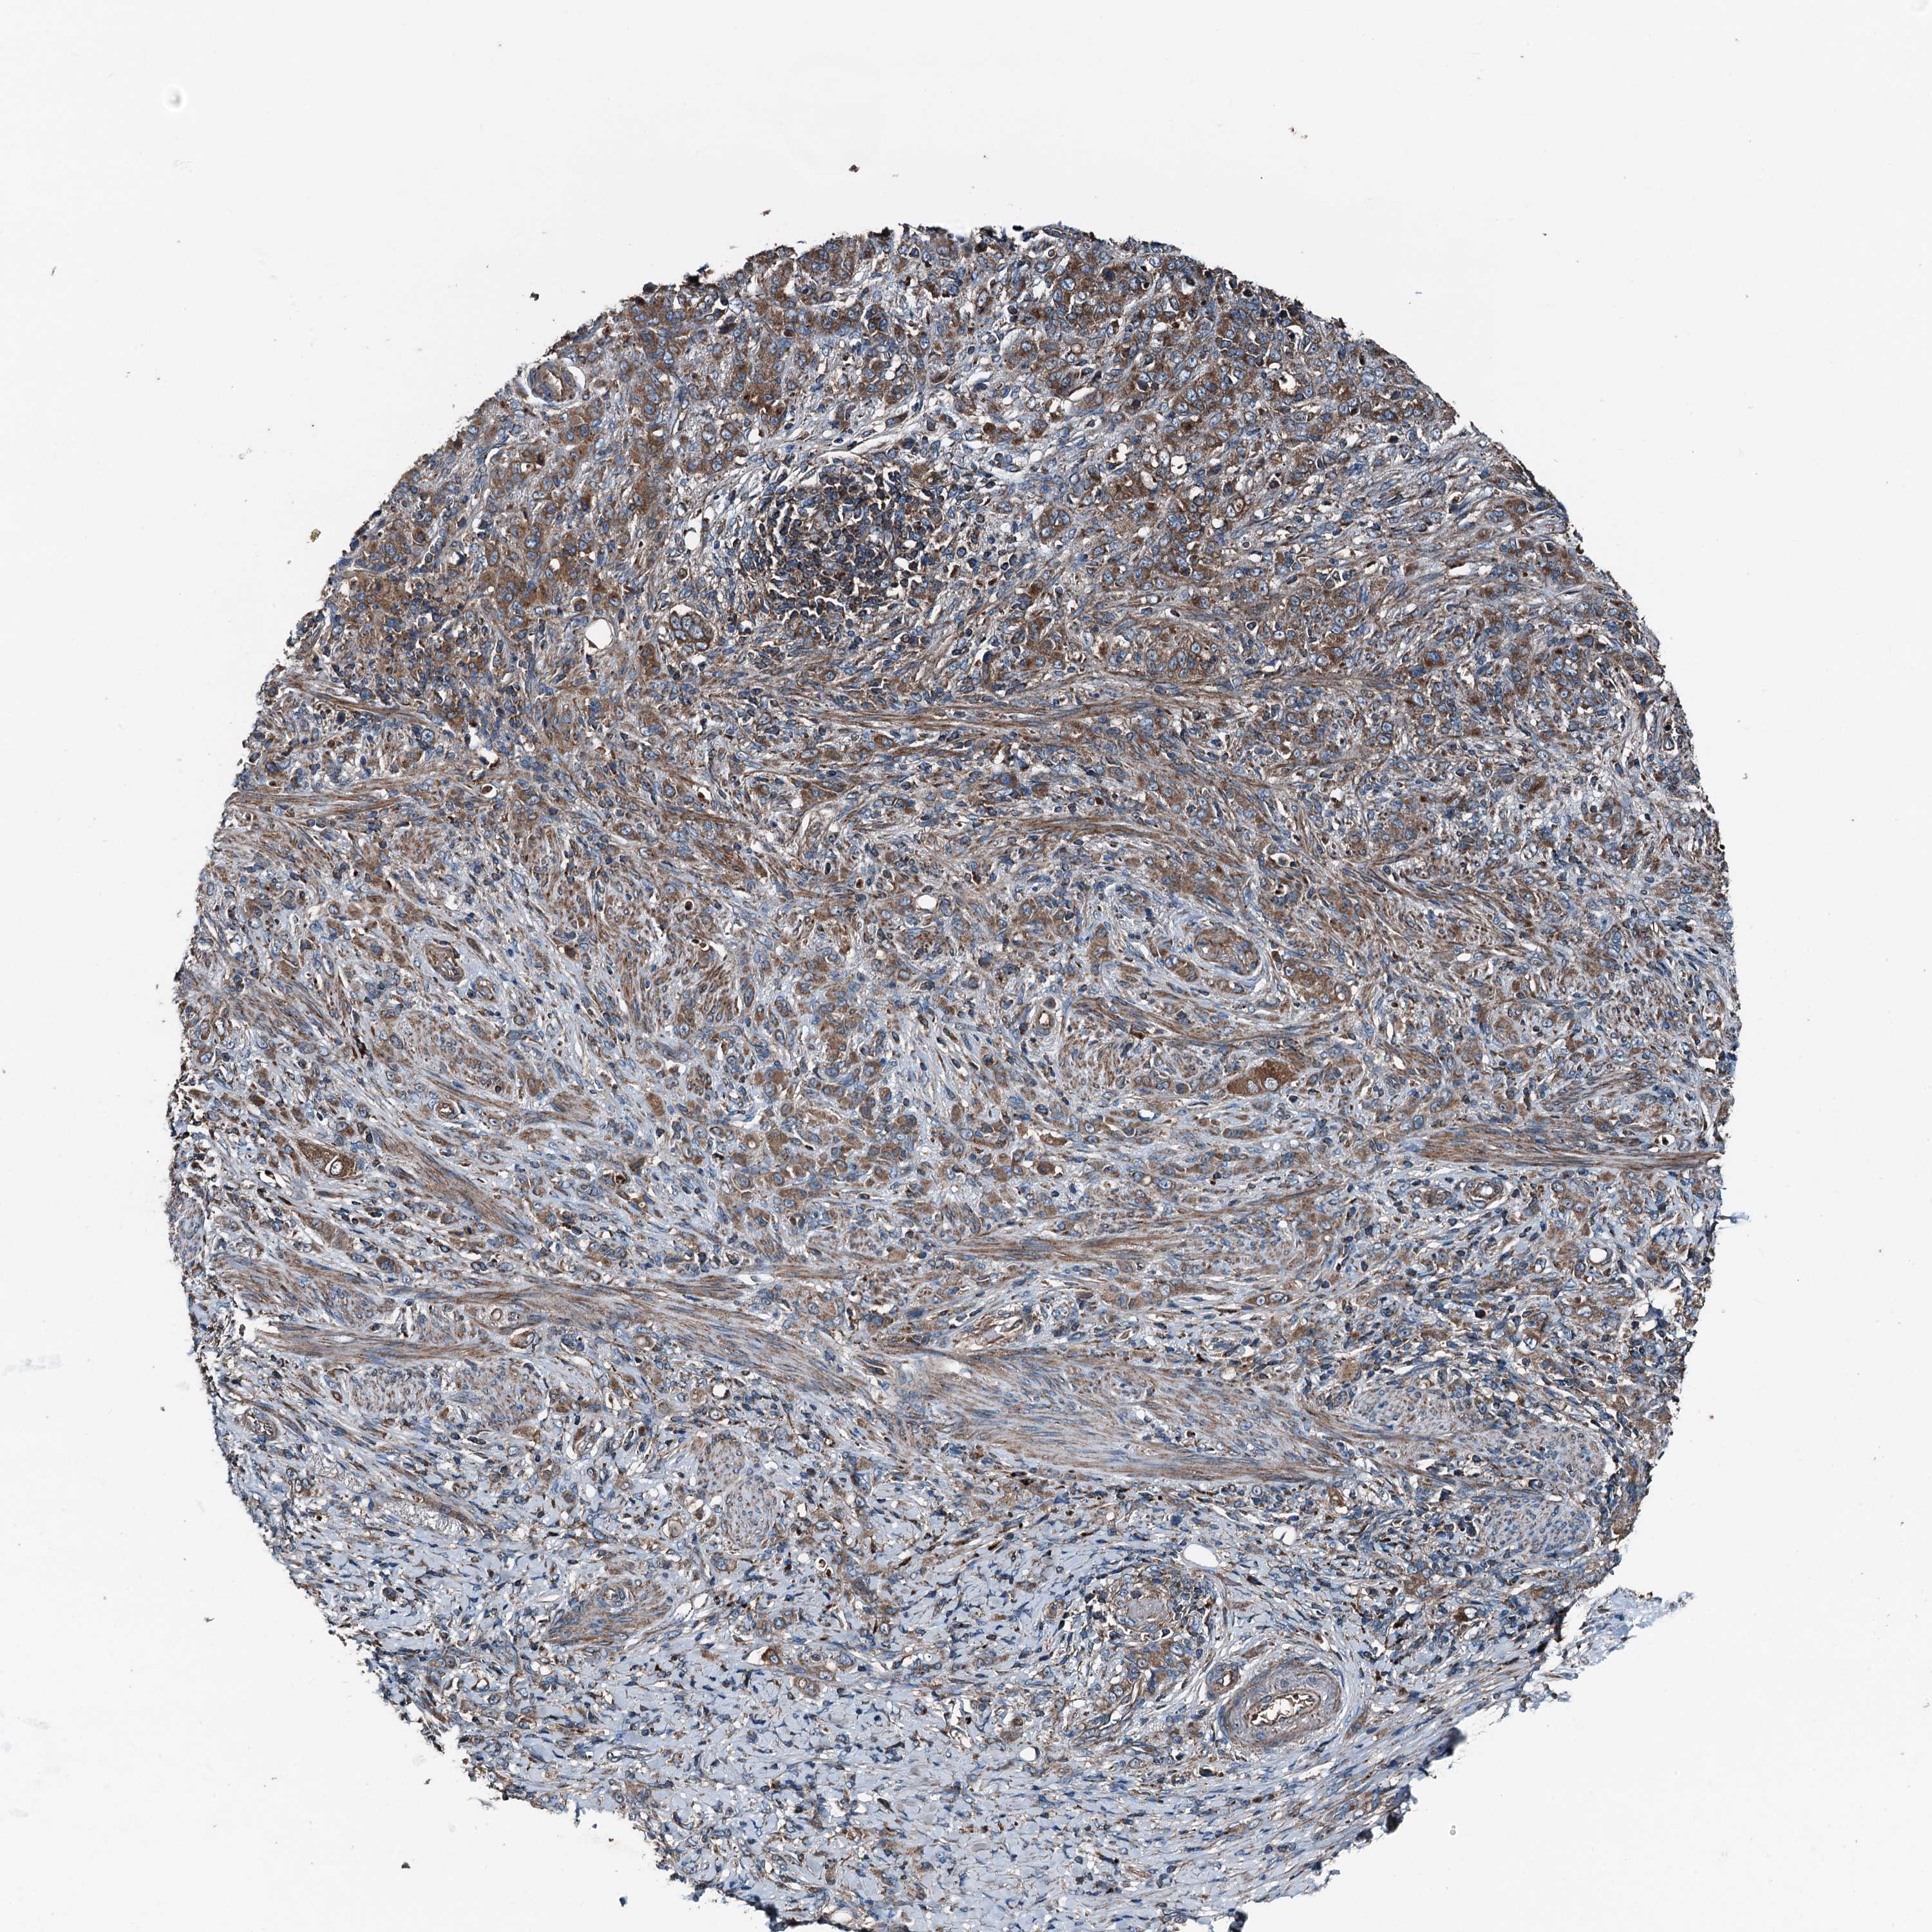

STOMACH CANCER - Protein expressioni

A mouse-over function shows sample information and annotation data. Click on an image to view it in a full screen mode. Samples can be filtered based on level of antibody staining by selecting one or several of the following categories: high, medium, low and not detected. The assay and annotation is described here.

Note that samples used for immunohistochemistry by the Human Protein Atlas do not correspond to samples in the TCGA dataset.

Antibody stainingi

Antibody staining in the annotated cell types in the current human tissue is reported as not detected, low, medium, or high, based on conventional immunohistochemistry profiling in selected tissues. This score is based on the combination of the staining intensity and fraction of stained cells.

Each image is clickable and will lead to virtual microscopy that enables deeper exploration of all samples and also displays staining intensity scores, fraction scores and subcellular localization as well as patient and tissue information for each sample.

Antibody HPA041227

Staining

High

Medium

Low

Not detected

Intensity

Strong

Moderate

Weak

Negative

Quantity

>75%

75%-25%

<25%

None

Location

Nuclear

Cytoplasmic/membranous

Cytoplasmic/membranous,nuclear

Adenocarcinoma, NOS

Adenocarcinoma, High grade